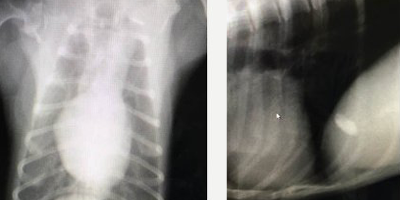

聴診、胸部レントゲン、心電図、胸部エコーなどにより、より高度な診察が可能となります。

心臓のサイズ・気管の位置・肺の状態 の検査を行います。